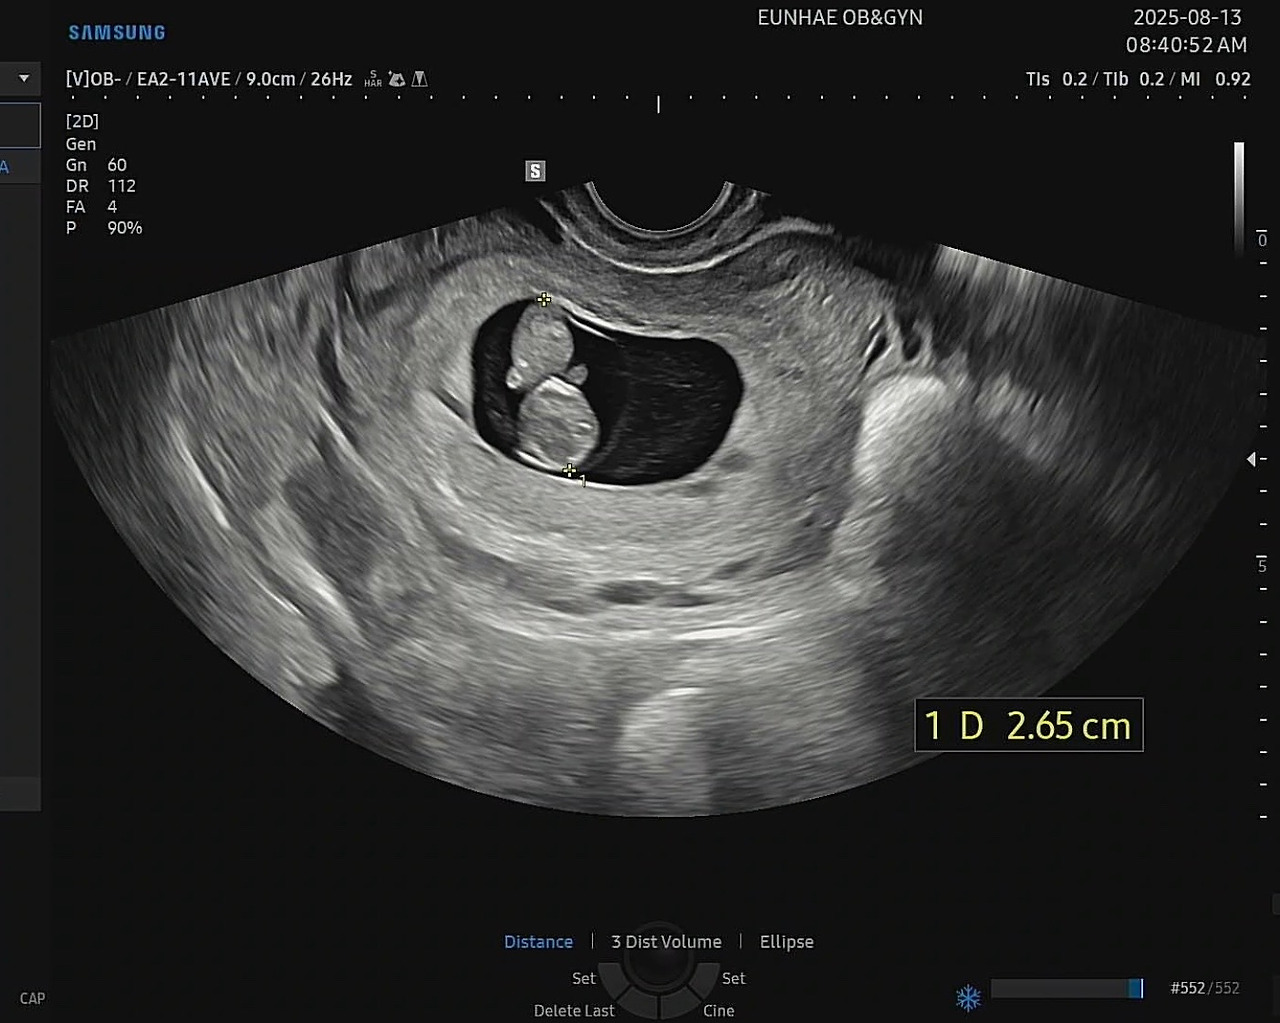

아내의 뱃속에 24주의 딸이 자라고 있습니다.

아내의 뱃속에는 24주를 막 지난 딸이 성장하고 있습니다. 아내와 함께 숙고해 ‘이수(李水)’로 이름도 지었습니다. 물처럼 유연하고 조화롭게 살아가길 바라는 마음을 담았습니다.